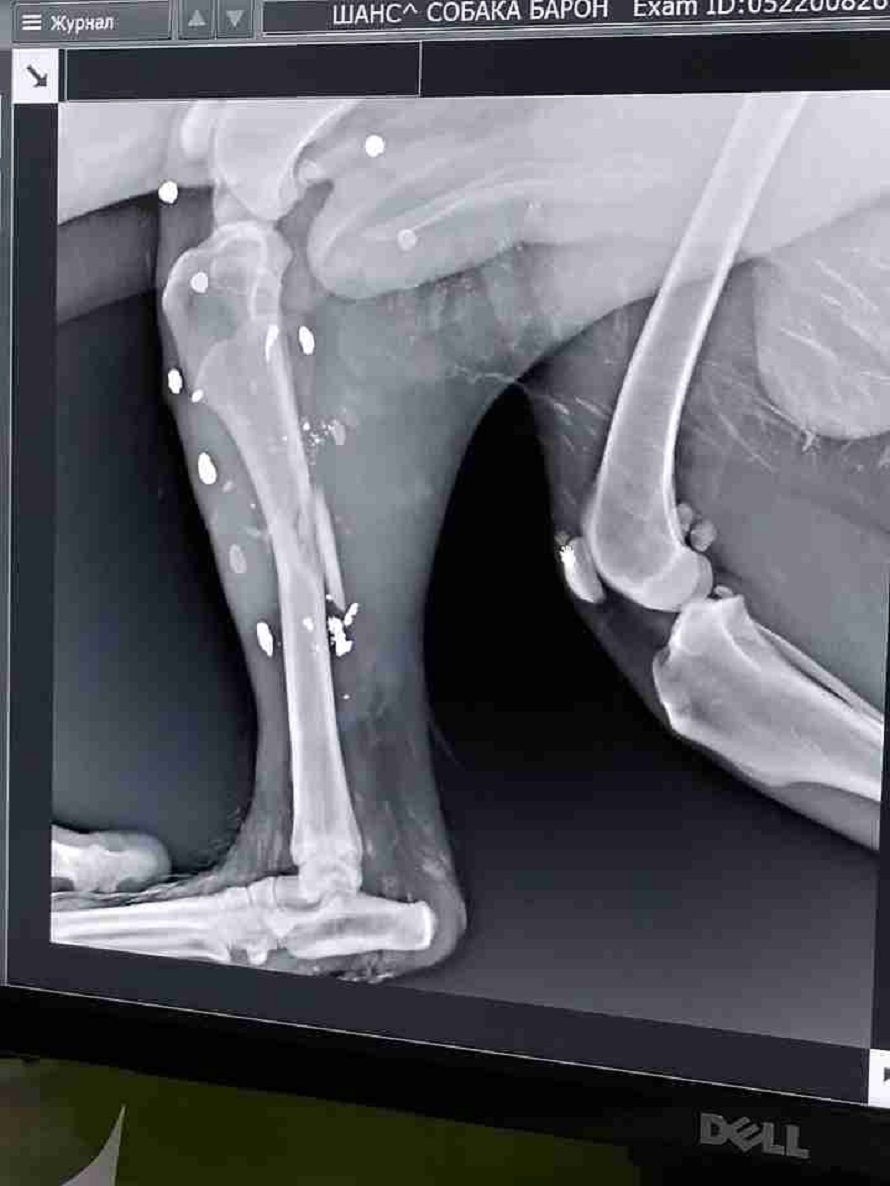

Однако, несмотря на то, что животное выжило, были получено тяжелые травмы: кости одной лапы полностью раздроблены.

Собаке уже провели срочную операцию, и, по словам зоозащитников, она была долгой и тяжелой.

«Переднюю лапу удалили. Заднюю собрали на пластину. Очень много осколков кости. В длину лапа потеряла 2 см, поэтому подсадили губчатое вещество, с помощью которого лапа останется нормальной длины», — пояснили в «Шансе».